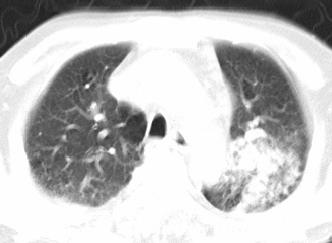

以下是引用xianxianzhongyi在2008-4-20 14:44:00的发言:[br]本人愚见:次病例短短两月的时间,呈现如此大面积实变,病变增长过于迅速,此其一。其二,病变在动脉早期既有明显强化。其三,左上叶后段及下叶背段多叶受累。其四,肺门及纵隔内未见明显肿大的淋巴结。估计层面较厚段支气管显示不清。 诊断:炎性实变可能性大。

以下是引用光影相伴在2008-4-20 14:39:00的发言:[br]支持:1)左侧中央型肺癌伴左肺上叶阻塞性肺炎。、[br] 2)双侧少量胸腔积液。